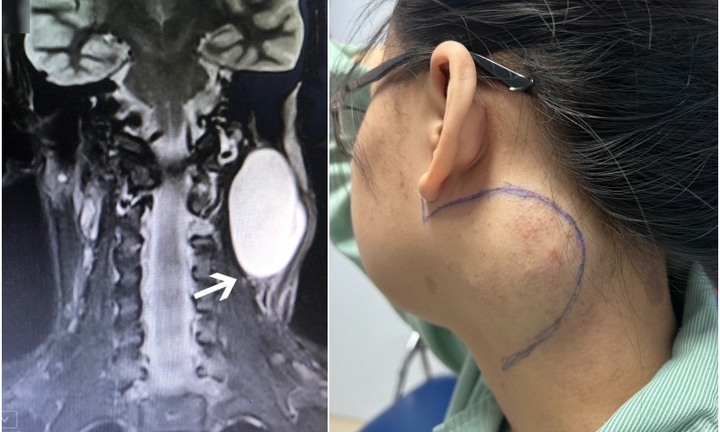

Cô gái 18 tuổi ám ảnh khối u lớn ở cổ suốt 7 năm

Cô gái 18 tuổi được mẹ đưa đi nhiều cơ sở y tế nhưng lần nào hai mẹ con cũng thất vọng quay về vì bác sỹ nói không mổ được do khối u nằm ở vị trí nguy hiểm.

Cô gái 18 tuổi được mẹ đưa đi nhiều cơ sở y tế nhưng lần nào hai mẹ con cũng thất vọng quay về vì bác sỹ nói không mổ được do khối u nằm ở vị trí nguy hiểm.